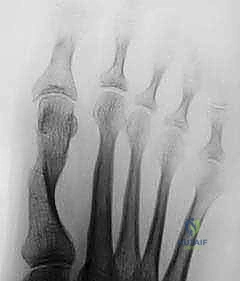

Standard posteroanterior, true lateral, and oblique radiographs of the affected digit are mandatory. The surgeon must scrutinize the images for joint space narrowing, periarticular osteophytes, malunited intra-articular fractures, and subtle joint subluxation. If the joint architecture is destroyed or severely incongruent, a soft tissue release will fail, and salvage procedures (arthroplasty or arthrodesis) must be planned.

Clinical & Radiographic Imaging

The following clinical and radiographic images demonstrate various presentations, surgical exposures, and outcomes associated with the release of posttraumatic digital joint contractures.